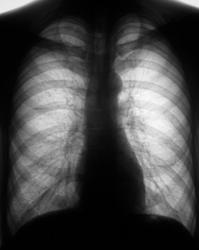

Пациент в 2007, 2008 гг. проходил профилактическую флюорографию - иллюстрации ниже. При прохождении флюорографиив 2009 г. "картинка" резко отличается от предыдущих.

1.Флюорограммы за 2007, 2008 гг. представлены, оценены, как норма.

2. Мужчина, 48 лет.

3. Жалобы на общую слабость. Больше жалоб никаких. В последнее время - кашель, мокрота беловатого цвета, имеются прожилки крови. Внешне - пациент недостаточного питания, анемичен, живет в семье.

По поводу личного мнения - больше склоняюсь, пока, в сторону абсцесса, однако сомнения терзают и весьма.

А разве не похоже на каверну с толстыми стенками?

Очень похоже,но при микроскопии "палки" не выявлены. Фтизиатр занимается пациентом вплотную. Уже рентгенологически обследовано "окружение" пациента, договорились с областной туб. больницей по поводу госпитализации. Но, вот полость какая-то не совсем типичная, хотя локализация и общий вид верхушки прямо указывают на "специфику".

Не должно быть туберкулёзом. Полость большая, а отсевов нет.

Как Вам версия распадающегося рака?

А я так хотела Вас возбудить!😊 Жаль-жаль.Туберкулёз тоже вполне подходит под эту картинку. Хронический очистившийся абсцесс тоже в диф.ряд. Могу и обосновать.